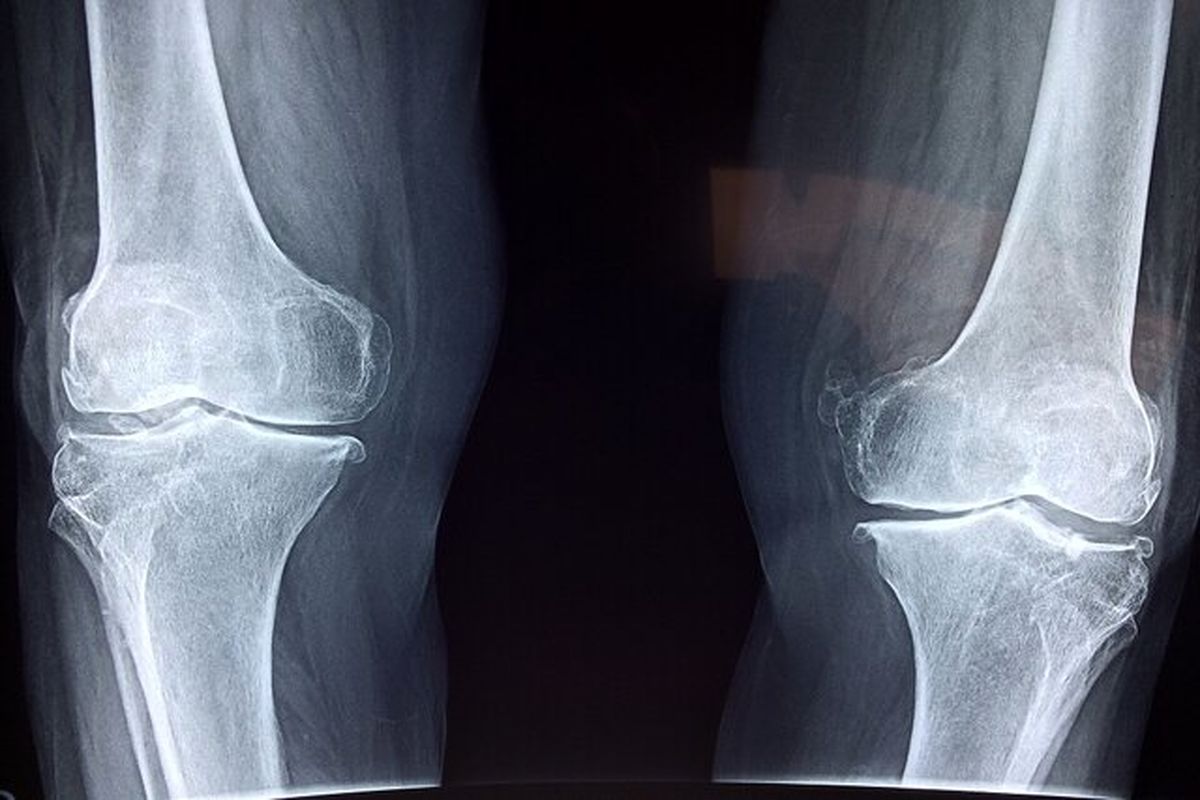

به گزارش ایسنا، دکتر سید مهدی میرغضنفری - معاون تعالی دفتر طب ایرانی و مکمل وزارت بهداشت با اشاره به شیوع پوکی استخوان خصوصا در سنین بالا، نگاه طب ایرانی به این بیماری را تشریح کرد و گفت: از دیدگاه مشترک طب ایرانی و فیزیولوژی مدرن، استخوان یک بافت زنده و پویا است که همواره در حال تخریب و بازسازی است و برای حفظ سلامت آن، ضروری است که از طریق جریان خون، غذای باکیفیت و مناسبی دریافت کند.

وی تاکید کرد: اگر خون کیفیت لازم را نداشته باشد، تغذیه مناسبی برای استخوان صورت نمی‌گیرد و مواد ضروری برای رشد و بازسازی به آن نمی‌رسد. در نتیجه استخوان به‌تدریج ضعیف‌تر می‌شود که به این حالت اصطلاحاً پوکی استخوان گفته می‌شود.